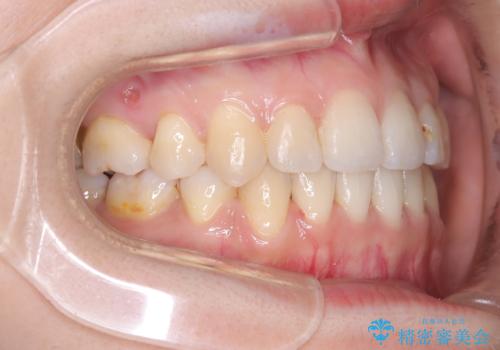

- 主訴:口元を下げて前突感を無くしたい、下の歯の凹凸も無くしたい

右側第二小臼歯、左側第一小臼歯、下顎両側第一大臼歯を抜歯しワイヤ-矯正を行いました。

骨格的顎の変位を認めたため、顔貌に対しピッタリ上下の歯の正中を合わせることは難しいと説明し、上下左右計4本小臼歯を抜歯しワイヤー矯正治療を行いました。